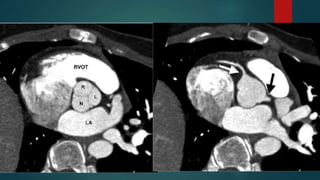

• #28 oblique CT image at the level of the aortic valve demonstrates right (R), left (L), and noncoronary (N) cusps CT image obtained at a slightly more cranial level shows the origins of the right (white arrow) and left (black arrow) main coronary arteries